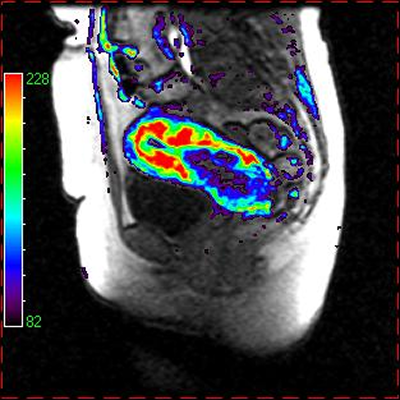

DCE-MRI permeability map color overlay on MRI in cervical cancer (left) and brain tumor (right). Data courtesy of Dr Nick Ferris, Peter MacCallum Cancer Center, Australia.